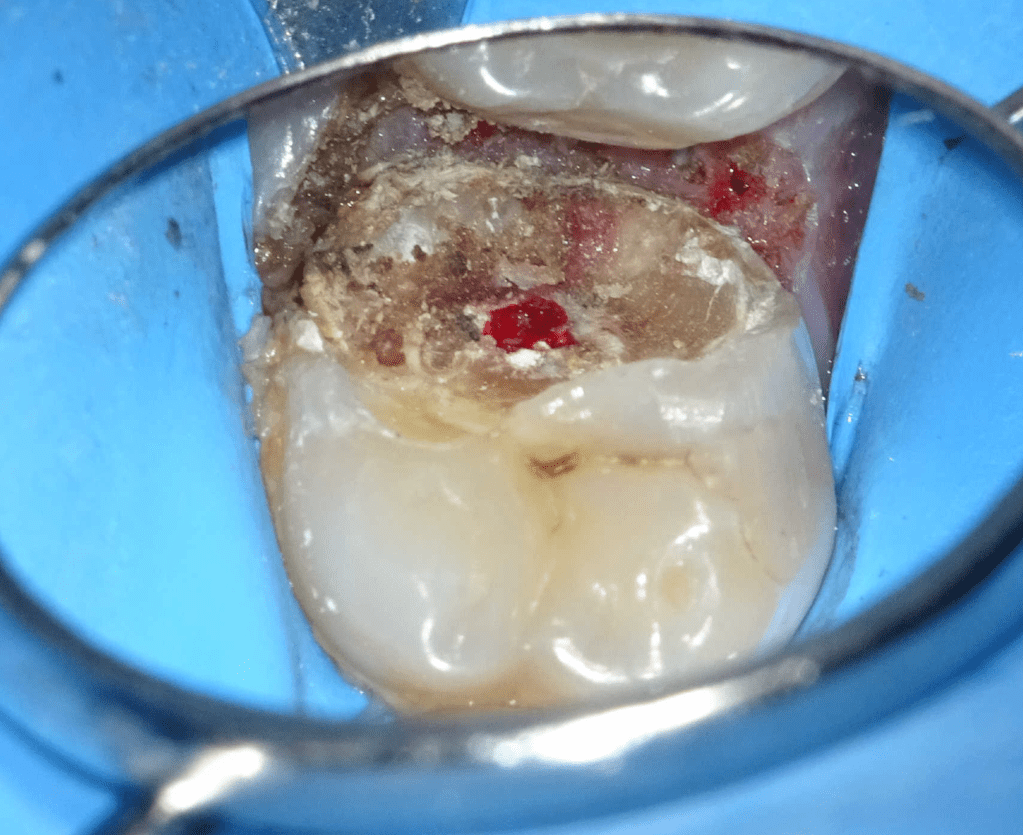

Pulpotomía biodentine + reco preendio